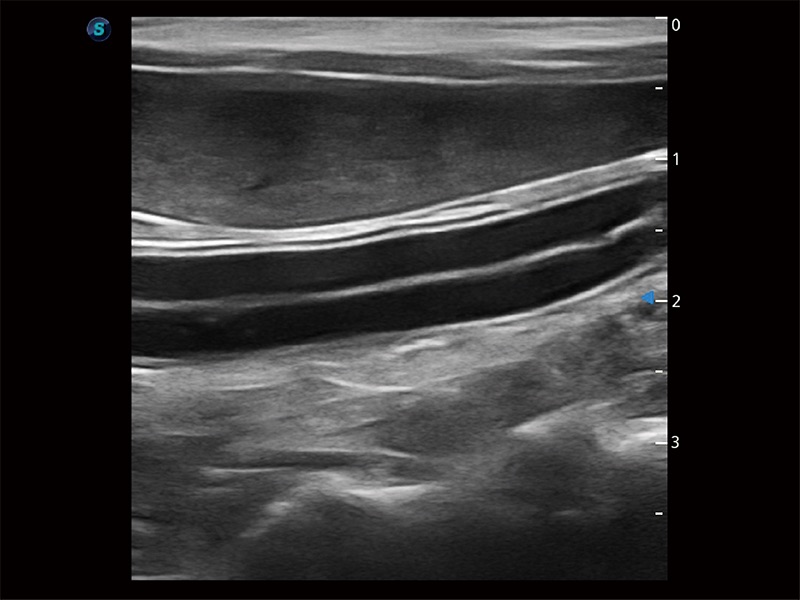

优异的基础图像

ProPet 80 全新的动物超声智能软件和丰富的探头群,为动物医生提供了高清晰度和精细分辨率的图像,无论在宠物、马科、畜牧还是实验室动物等应用中都可以轻松应对,为您的日常工作带来满意的体验。

(犬)肠道

(犬)肾脏显微血流